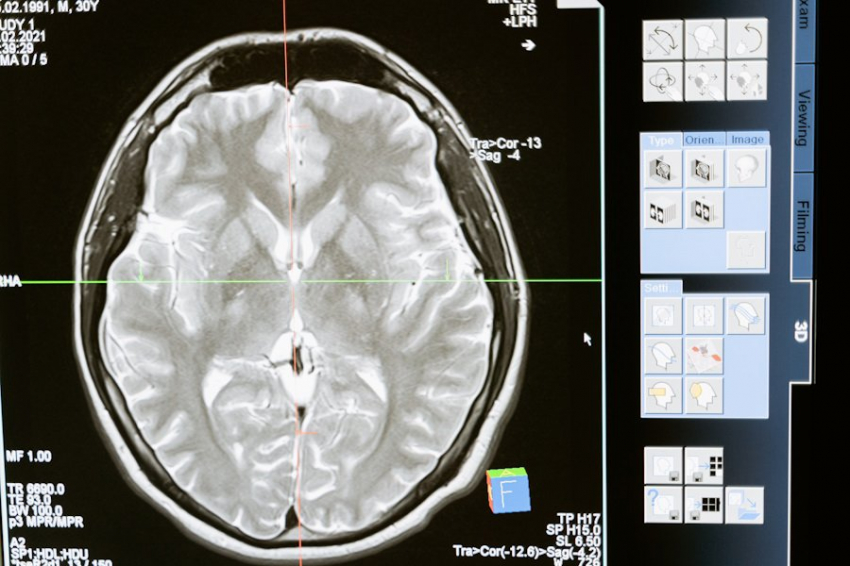

Измененные состояния сознания, вызванные тяжелыми травмами головы или опухолями мозга, часто лишают человека возможности общаться или реагировать на внешний мир. Это делает задачу оценки уровня сознания чрезвычайно сложной.

Следующий этап — регистрация электрических сигналов мозга. Их фиксирует специальное оборудование, преобразующее данные в музыкальные звуки. Звуковой генератор создаёт мелодии, которые отражают уровень активности мозга пациента. Если музыка становится более ритмичной, это свидетельствует о росте активности сознания.